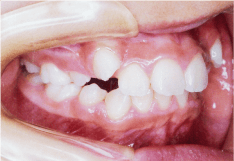

- 叢生(そうせい)

- 歯がでこぼこに並んでいる状態のことをいいます。この状態は歯磨きのときにブラシがしっかりと届きにくく歯垢が残りやすいため、虫歯や歯槽膿漏の原因になります。